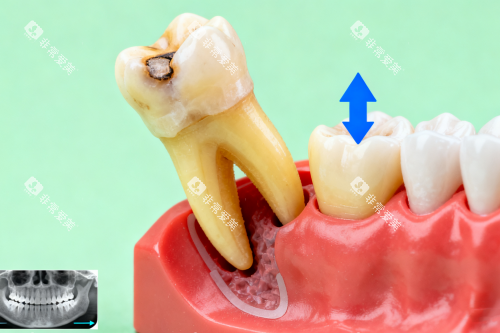

更隐蔽的危害在于,横向智齿会缓慢而持续地推挤前方的第二磨牙。

这种压力可能导致邻牙牙根吸收,较终使原本健康的牙齿松动脱落。

临床观察发现,约60%的横向阻生智齿会对邻牙造成不同程度的损害,而这种损害往往在出现明显症状时已相当重的。